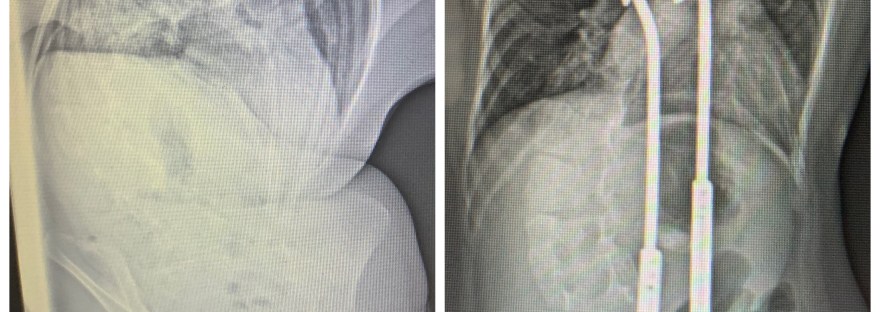

June is Scoliosis Awareness Month. June is Scoliosis Awareness Month! Wear green National Scoliosis Awareness Month: National Scoliosis Awareness Month occurs yearly in June to highlight the growing need for education, early detection, and awareness about scoliosis and its prevalence within the community. The campaign also unites scoliosis patients, families, physicians, clinicians, institutions, and related… Continue reading June is Scoliosis Awareness Month